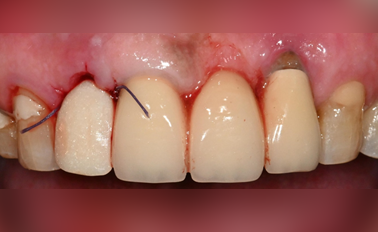

이 글의 핵심 요약 대상: 눈에 잘 띄는 앞니 상실로 인해 외관상 자연스러움과 기능을 동시에 회복하고 싶은 분 핵심: 1mm 미만의 얇은 **순측 골벽(입술 쪽 뼈)**을 보존하며 정밀하게 식립하는 고난도 기술 강점: 0...

안녕하세요. 진료실에서 가장 안타까운 순간 중 하나가, 앞니 임플란트를 이미 한 번 했는데 재수술을 해야 한다는 이야기를 듣고 오시는 경우입니다. “임플란트는 한 번 하면 평생 쓸 줄 알았는데, 왜 또 해...